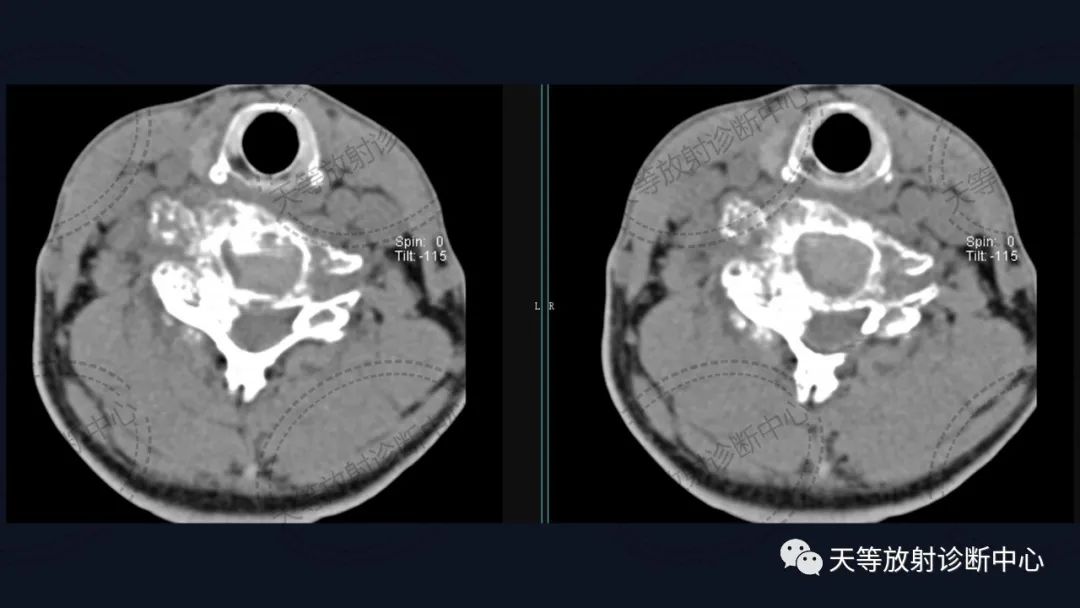

男性,54岁。男性,54岁。

椎体骨质破坏并见大量软骨基质形成

软组织窗骨质破坏呈溶骨性、外生性生长,内部见大量钙化影。

骨质破坏呈溶骨性,大量钙化,肿块向外生长,局部突入椎管内。

病例1:上图:软骨肉瘤。CT显示椎管及其附件骨质溶骨性破坏,椎体周围软组织肿块并含大量钙化影,钙化呈斑片状、斑点状不定型。整个肿块外生性生长为主,局部突入椎管内。